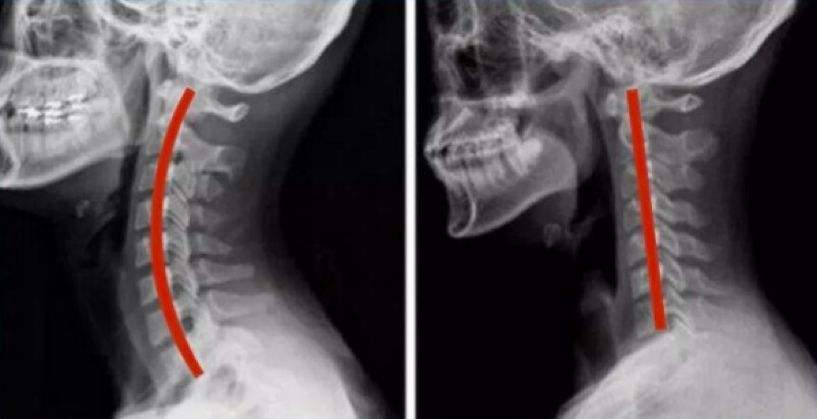

但长期低头,会改变颈椎的正常生理弯曲度,正常的是一个C状的,而亚健康人群,基本都有颈椎生理弯曲变直的问题。生理弯曲的改变,长期会引发骨质增生,椎间盘退变,椎管狭窄等情况,也就是向严重的颈椎病发展。

左图是正常的C型生理曲度